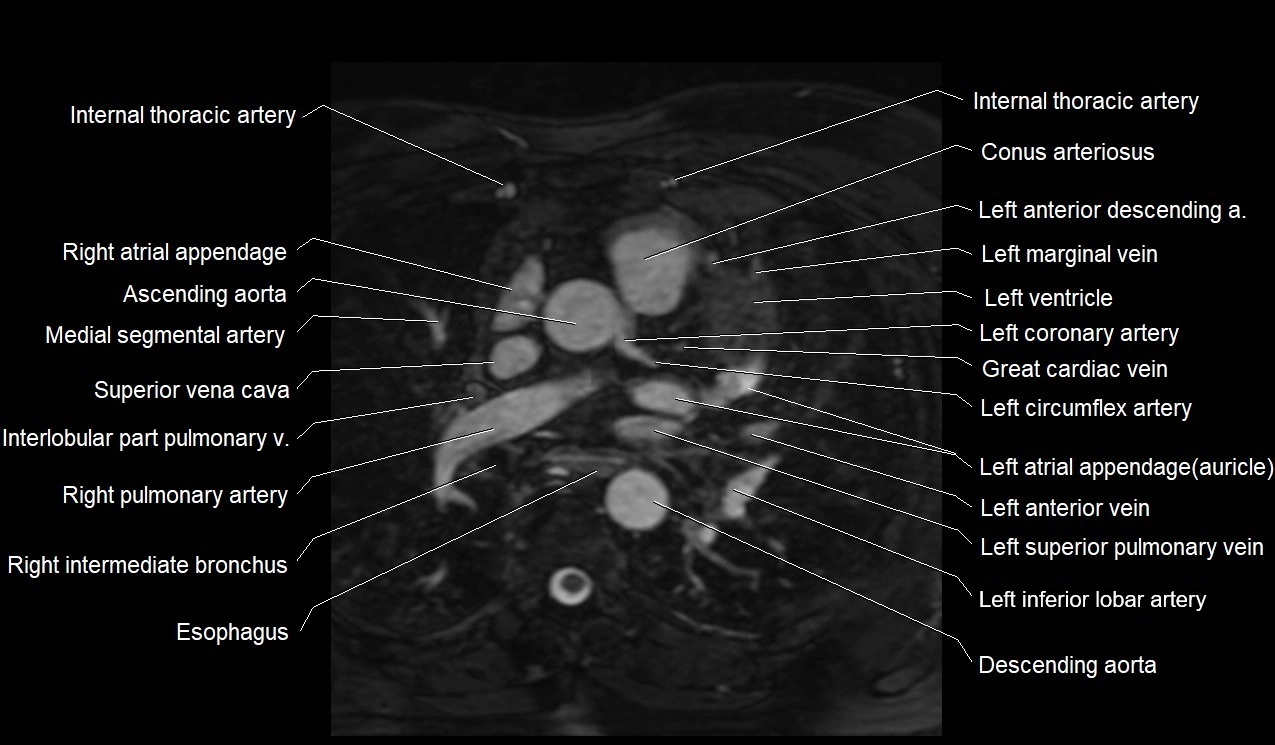

MRI image